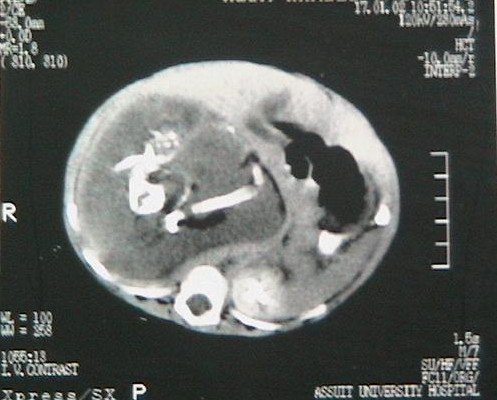

The baby born at the Queen Elizabeth Hospital in Kowloon, Hong Kong, had foetuses with 8 to 10 weeks of gestation, reports abc news. Each of the foetuses growing inside the nearly 9-pound baby girl had four limbs, a spine, rib cage, intestines, anus and an umbilical cord connected to a single placenta-like mass.

It is understood that the fertilised eggs were absorbed into the baby's body as it grew and lodged between her liver and left kidney. Barely three weeks old, the baby had to undergo a surgery to remove the "babies" inside her.